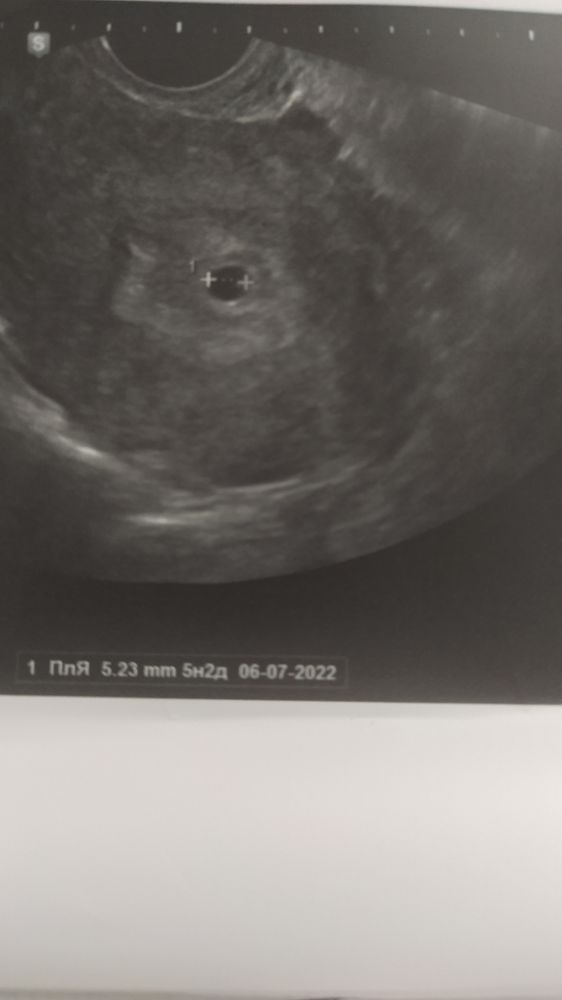

Впервые такое короткое заключение дают, прошло быстро, молча. Спросила про срок, говорю, что прям ровно 4 недели, узистка нет практически 5 и все, ну можете через 2 недели прийти. Капец, что скажите, я надеялась хотя бы эмбрион увидеть

В 5.2 ходила. Плодное яйцо только и то меньше вашего. Желточного мешка тоже не увидеди. Какой ещё эмбрион а 4н вы ждали? Тоже самое прийти через 2 недели сказали. Все что можно было найти в 4-5н вам нашли. И даже больше чем у многих. Зря жалуетесь.

Ваше УЗИ на 4 эмбриональных,а не акушерских это акушерских 6,через неделю будет эмбрион и сб уже

Ходила в 5+3 чтобы посмотреть, маточная ли, увидели только ПЯ. При хгч чуть за 1000 этого вполне достаточно. Но я почему-то успокоилась, в следующий раз уже пошла в 8+3 - там был и жм, и эмбрион и сердечко билось) узист даже сказала, что плацента начала формироваться по задней стенке. Все у вас нормально, что увидела, то и написала)